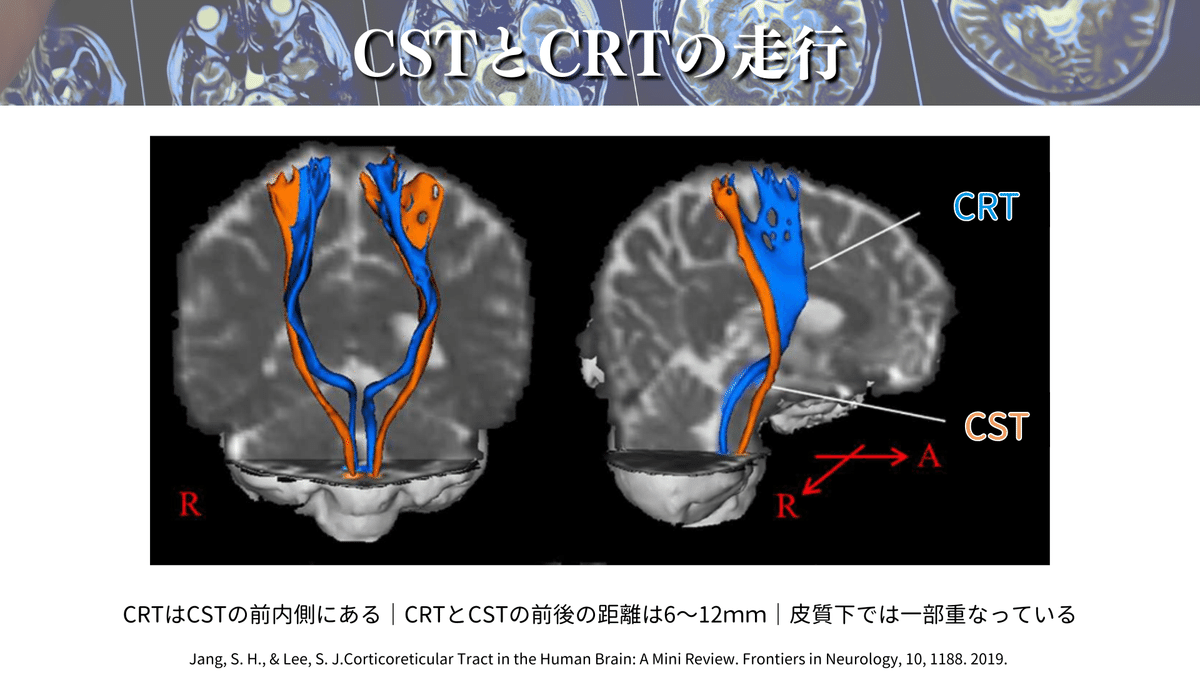

ということで、今回は「 Corticoreticular Tract in the Human Brain: A Mini Review. 」を読んで、得られた知見とこれまで僕が学んできた知識を織り交ぜながらCSTが読影できるように書いていこうと思います‼️

CSTの走行は養成校でも習っており、参考書でもよく取り上げられているのでイメージはついていました。一方で、CRTの詳細な走行を解説している参考書は少ないので、この論文に出会ったときに「これじゃん😳✨」と思ったからです!

さらにこの論文では、上図のように拡散テンソルトラクトグラフィー(DTT)を用いてこれらの経路を視覚的に確認できる点が魅力です😍

CSTとCRTの理解を深めることで、CVD後の運動障害の評価や介入、予後予測などに役立つかもしれませんね🫡

この記事では、CSTのMRI読影について解説していきますね👍

まずは全体像を見ていきましょう👀

青:CRST

オレンジ:CST

これらの視点を持つことで、よりイメージがしやすいのではないでしょうか😉?